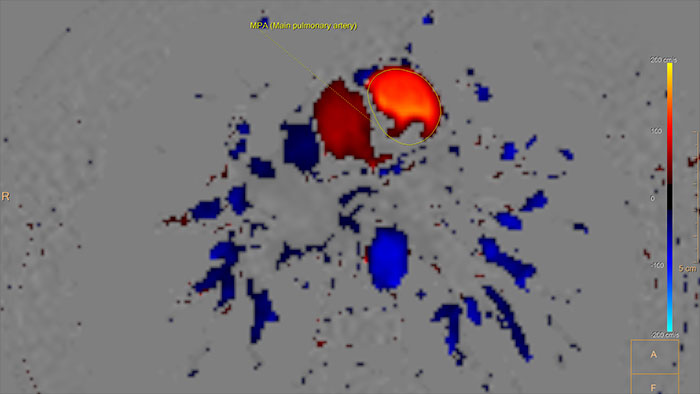

Visualizing and quantifying blood flow dynamics

Supports visualization and quantification of blood flow dynamics by assisting in review of MR phase-contrast data, on vascular region of interest segmented manually, or semi-automatically. Qflow analysis is integrated as part of MR Cardiac Suite allowing flow and functional analysis in one suite with combined reporting.

Benefits